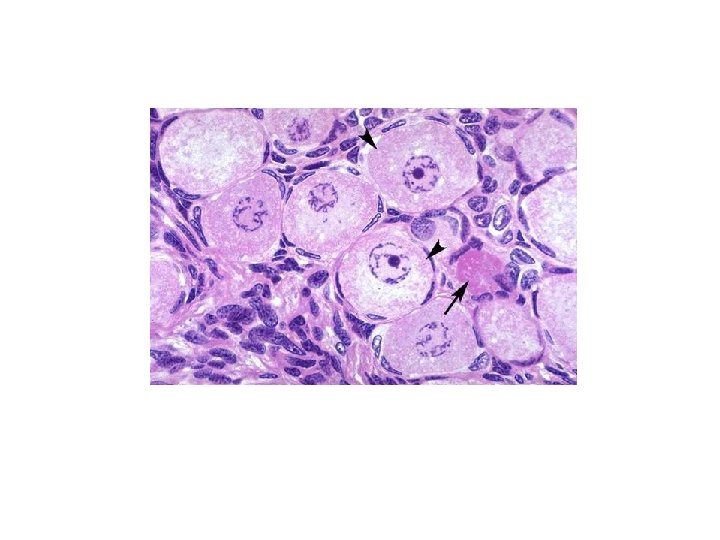

Corpus Hemorrhagicum Ø Following ovulation the remainder of follicle collapses and some ruptured blood vessels leak into follicular cavity and forming a clot that is known as corpus hemorrhagicum Corpus Luteum ² After removing the clot by phagocytes a temporary hormone secreting structure formed by granulosa cells and theca interna cells known as corpus luteum ² Granulosa cells hypertrophy into large pale staining granulosa-lutein cells with organelles necessary for steroid production ² They constitute about 80% of the cells of corpus luteum ² These cells produce progesterone and convert androgen produced by theca-lutein cells into estrogens

Corpus Luteum J Theca interna cells form theca-lutein cells which are smaller and darker staining than granulosa-lutein cells J Located in folds of cells in perimeter of corpus luteum form about 20% of cells population and are highly vascularized J Produce estrogen, progesterone androgens J If pregnancy does not occur corpus luteum of mensturation survives only 10 -14 days J In pregnancy it enlarges greatly due to HCG and lasts 6 months and called corpus luteum of pregnancy J Corpus luteum of pregnancy grows to a 5 cm diameter structure

Corpus Albicans [When the corpus luteum degenerate it is invaded by fibroblasts which manufacture collagen type I and form a fibrous structure known as corpus albicans [Large ones form after pregnancy and smaller ones after each ovulation [On the surface of ovary remnants of corpus albicans is visible as a scar